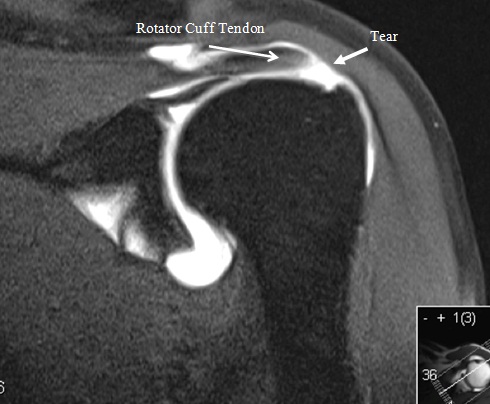

A rotator cuff tear was diagnosed using the following for other signs of rotator cuff tendon pathology. reaccumulation of the fluid and persistent symptoms. Intramuscular cysts of the rotator cuff, although an ... Get Doc

Rotator Cuff Tears: Clinical, Radiographic, And US Findings

23 different signs, symptoms, and tests were as-sessed in the 10 studies, no definite conclusion about individual tests could be reached, since too tendon, are also considered secondary signs of rotator cuff tear (Fig 20). In fact, Jacobson et al ... Return Doc

Identify a Rotator Cuff Tear on MRI it could represent early disease in which symptoms have not yet developed\\മ Shows that asymptomatic shoulders with RCT on MRI can have normal function and you should not base management on MRI alone. Impingement Signs ... Get Content Here